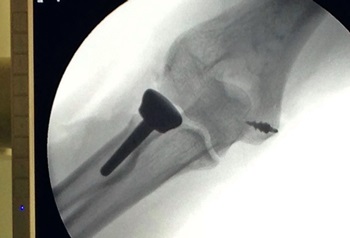

Dia 01 de setembro, foi realizado no Hospital Maicé um procedimento inédito na área de ortopedia. A equipe, comandada pelo médico ortopedista especialista em ombro e cotovelo Andre Luiz Dall Agnol realizou a implantação de uma prótese de cabeça de rádio, garantindo a reconstrução da articulação e a rápida recuperação do paciente.

“O procedimento foi realizado na última quinta. Atendemos uma paciente internada com vários traumatismos. Ela foi vítima de acidente de trânsito. Foi realizado primeiro o procedimento emergencial e depois o definitivo, com a reconstrução da parte ligamentar e a utilização de uma prótese de cabeça de rádio. A paciente fez uma fratura complexa em uma das articulações do cotovelo e, nesta articulação, não havia mais possibilidade de reconstrução devido a multifragmentação da fratura. Então foi optado, junto com a equipe, pela prótese”, explica.